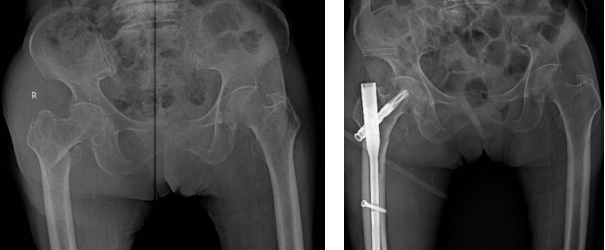

• Phương pháp kết hợp xương bằng đóng đinh nội tuỷ: Phương pháp này được chỉ định cho những trường hợp gãy xương phức tạp, gãy không vững và có thêm mảnh rời. Cụ thể, một số loại đinh nội tủy được sử dụng phổ biến gồm: Gamma, PFNA​​​​​​​

Đinh nội tuỷ PFNA